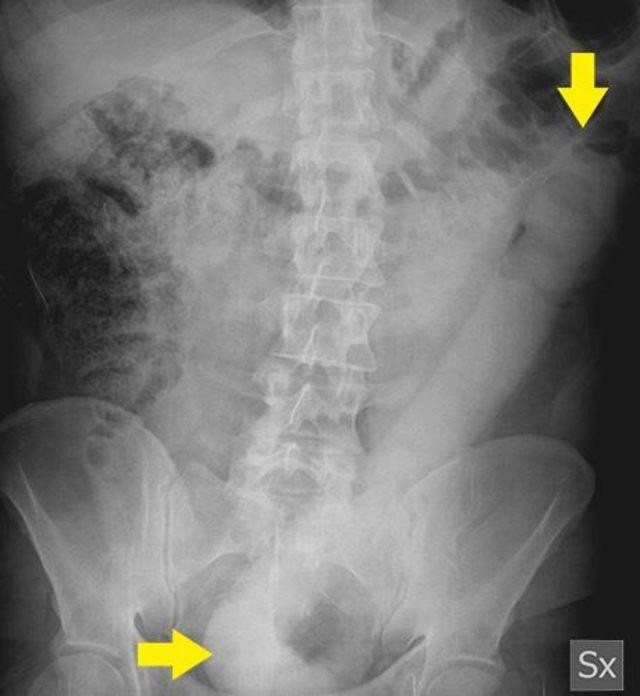

Hastaneye kaldırılan adamın içinden seks oyuncağını çıkaramayan doktorlar röntgeni görünce yeni bir yöntem izledi.

Haberde, adamın karın ve mide ağrısı çektiği ifade edilirken doktorlar röntgen sonuçlarını görünce şaşkına döndü.

Hem geniş hem de yaklaşık 58 santimetrelik uzunluğuyla adamın göğüs kısmına kadar giren cismi çıkarmak için doktorlar ameliyata girdi. Fakat Great Metropolitan Hastanesi’nde yaşanan olayda doktorlar kayganlaştırıcı ve benzeri sistemlerle nesneyi çıkarmayı başaramadı.

Acı içinde kıvranan adamın içindeki nesnenin uzun olması dolayısıyla çıkarılamadığını tespit eden doktorlar yeni bir yöntem denedi.